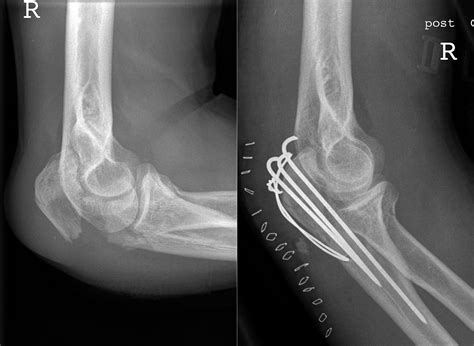

• Olecranon Fractures: Fractures of the olecranon can occur due to direct trauma, such as a fall onto an outstretched hand or a blow to the elbow. These fractures can be painful and may require surgical intervention to restore function.

• Surgical Intervention: In severe cases, surgery may be required to repair fractures, remove damaged tissue, or stabilize the joint.